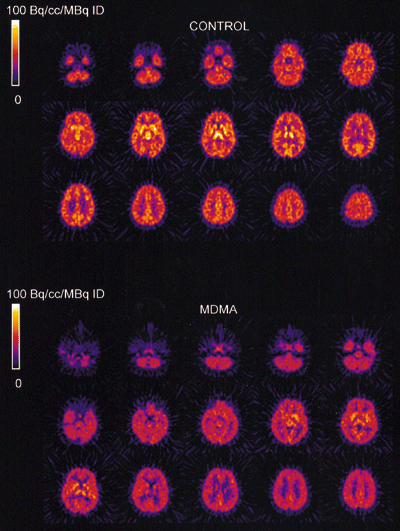

The injected doses of radioligands did not differ significantly in the two groups (table 3). We plotted representative time-activity curves with model fits for [11C](+)McN-5652 and [11C](-)McN-5652 for the two groups (figure 1). Although control and MDMA participants had similar transport of [11C]McN-5652 from blood to brain (K1) for all brain regions assessed, MDMA users had significant global decreases in DVs for specific binding of [11C]McN-5652 (p=0·011), which suggests that they had a lower density of brain 5-HT transporter sites than participants in the control group (figure 2). The covariance effects of age and sex were not significant (p=0·95 and p=0·16, respectively). Decreases of regional brain DVs in human MDMA users (figure 3) are consistent with PET findings in MDMA-treated baboons.23

|

Shown are measured and model fitted data for both [11C]McN-5652 enantiomers. |